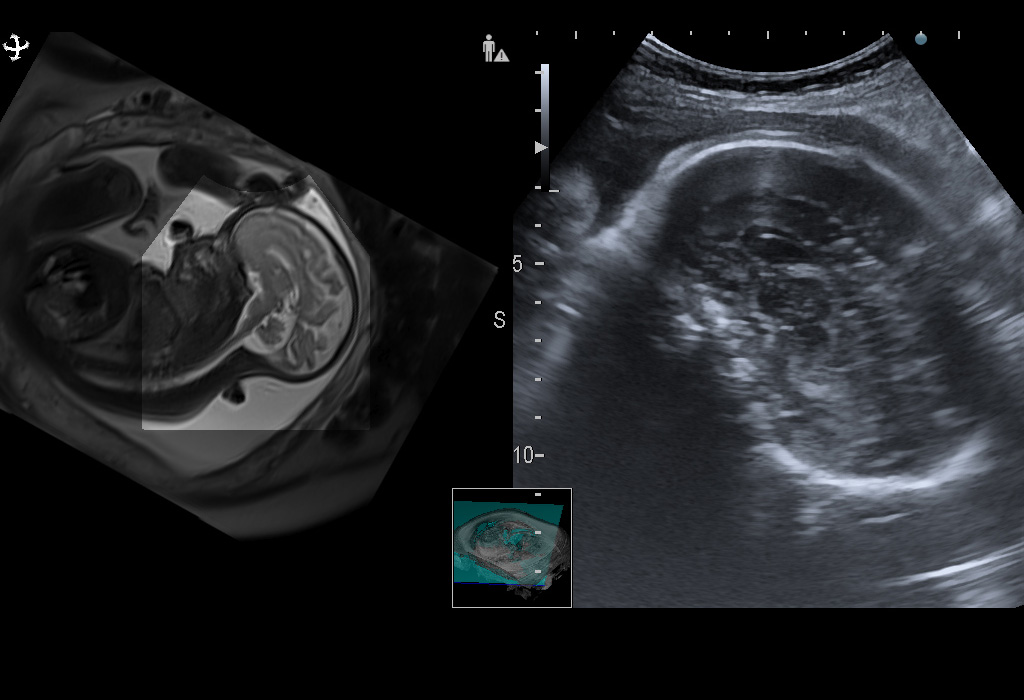

Синхронизация

В системе доступна синхронизированная визуализация с МРТ или КТ. Возможности ультразвукового аппарата расширяются за счет использования снимков, полученных другими методами. Используя пакет программ Real-time Virtual Sonography, можно совмещать снимки УЗИ с картинками, полученными методом компьютерной и магнитно-резонансной томографии. Программы для совмещения дополняются опциональным пакетом 3D Sim-Navigator.

Мощный функционал системы позволит получать четкие снимки без шумов и артефактов, а также совмещать их в режиме реального времени с данными других приборов. Это откроет широкие возможности для проведения самых сложных исследований. В системе можно моделировать воздействие радиочастотной абляции на новообразование. Так можно предсказать, насколько эффективной окажется процедура. Сложно найти более функциональное оборудование.

Головной мозг плода. Синхронная мультимодальная визуализация с помощью технологии Real-time Virtual Sonography (RVS) позволяет комплексно оценить головной мозг плода